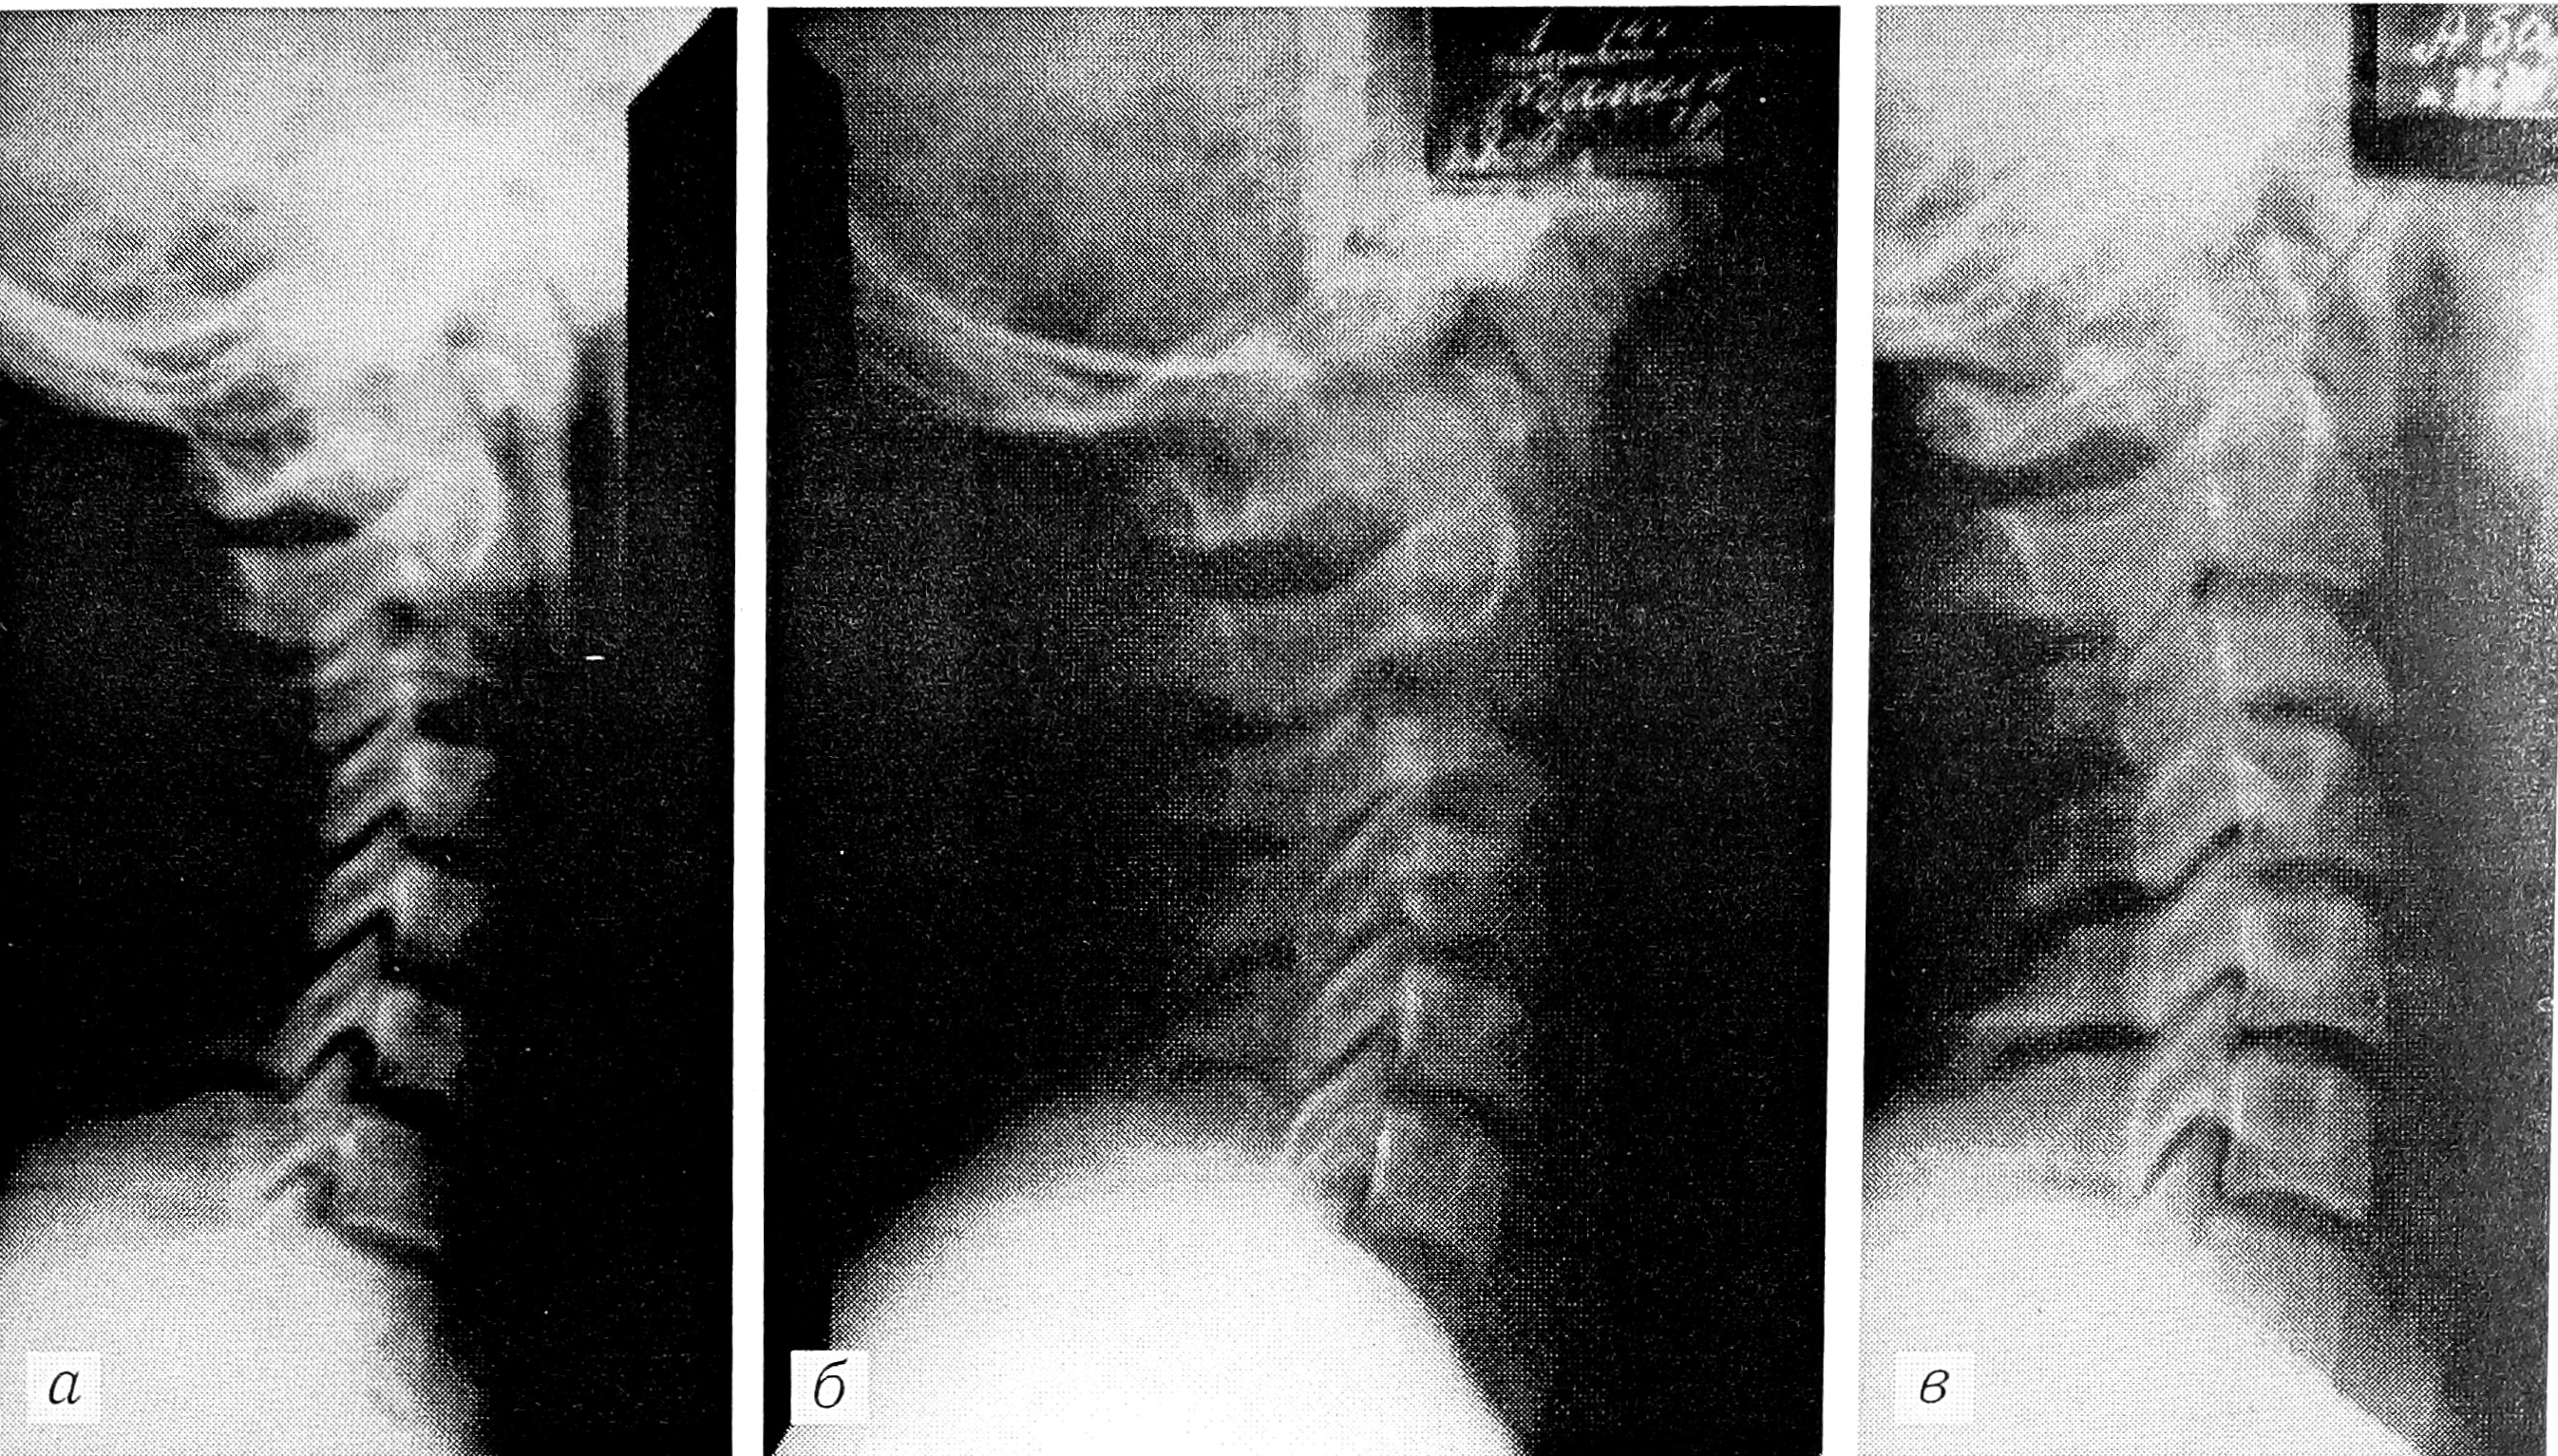

Эозинофильная гранулема (52 больных) на нашем материале составила более 20% всех опухолей и опухолеподобных поражений позвоночника у детей. В 88% случаев было поражено тело позвонка. По рентгенологической картине выделены три фазы течения процесса: первая — фаза остеолиза, вторая — патологического перелома и образования плоского позвонка, третья — исхода патологического процесса (рис. 4 на вклейке). В первой фазе определяется солитарный или множественный очаг деструкции остеолитического характера, отграниченный от смежных отделов кости нечетко выраженной зоной склероза. Форма очага округлая или овальная. В позвонке он занимает большую часть тела и вызывает вздутие, истончение коркового слоя. Длительность фазы остеолиза — около 2,5 мес. Во второй фазе формируется плоский позвонок с равномерным снижением его высоты (патологический перелом). Длительность этой фазы — в среднем 6 мес. Фаза исхода — неполное восстановление высоты позвонка при полном восстановлении его структуры. Продолжительность этой фазы для позвоночника от 1 до 3 лет [8]. Диагностические трудности возникают в первой фазе и при атипичной локализации эозинофильной гранулемы. Важное значение для диагностики имеет динамика процесса.

Рис. 4. Больной 13 лет с эозинофильной гранулемой тела С3 позвонка.

Рентгенограммы (динамика процесса на протяжении 4 лет): а — остеолиз тела С3, б — формирование плоского позвонка, в — исход.